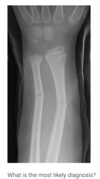

35

diagnose

green stick fracture of the mid ulnar and radius